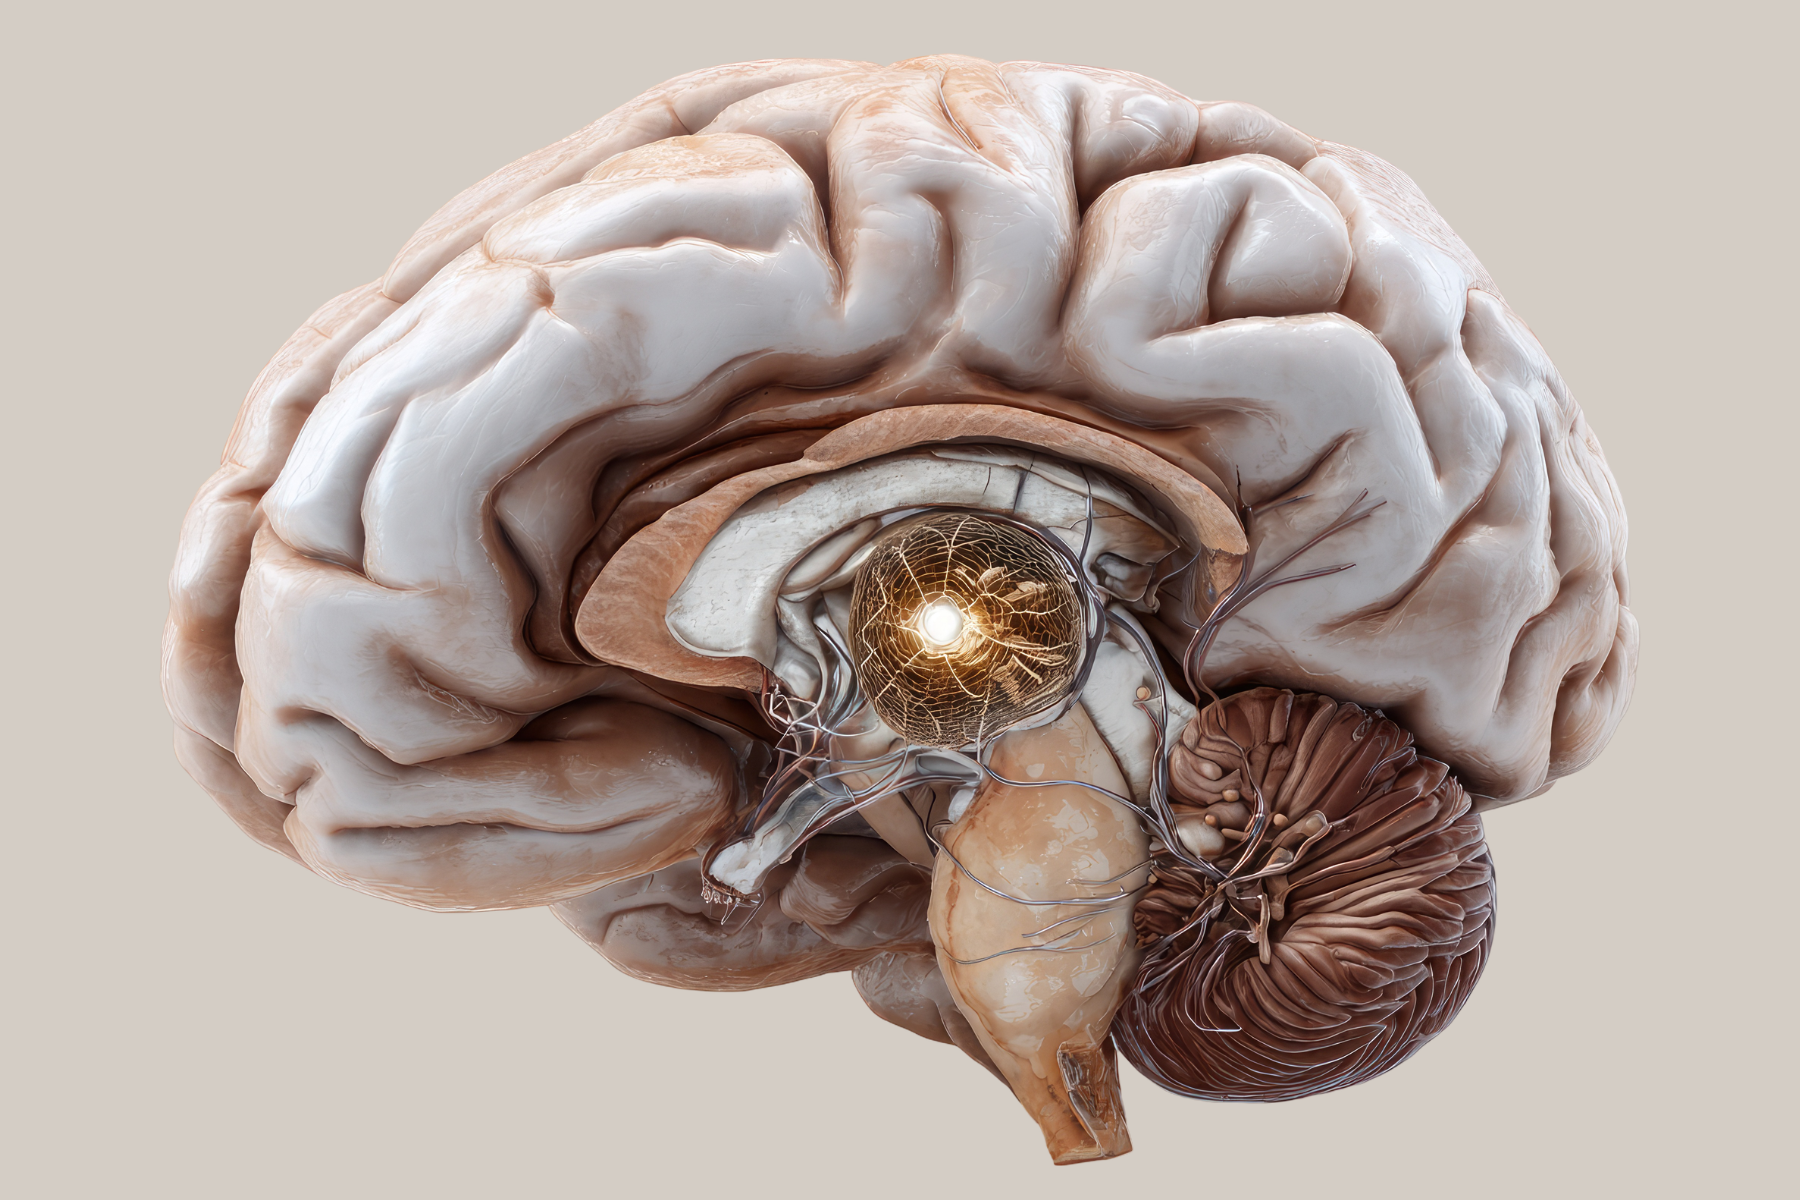

Endovascular neurointervention is an advanced, minimally invasive approach used to diagnose and treat complex disorders of the brain and spinal blood vessels. At AB Skin and Neuro Centre, Dr. Ranjith G, a leading interventional neurologist in Manikonda, provides state-of-the-art endovascular procedures for conditions such as stroke, aneurysms, and vascular malformations.

Using high-precision imaging guidance and catheter-based techniques, Dr. Ranjith performs targeted procedures to restore blood flow, treat vascular abnormalities, and prevent life-threatening neurological complications. His approach focuses on minimally invasive intervention, faster recovery, and improved neurological outcomes for patients.

Modern endovascular techniques allow precise treatment of complex neurovascular conditions while avoiding major surgery and reducing recovery time.

Digital Subtraction Angiography (DSA) – Advanced imaging technique used to visualize blood vessels in the brain and spine for accurate diagnosis and treatment planning.